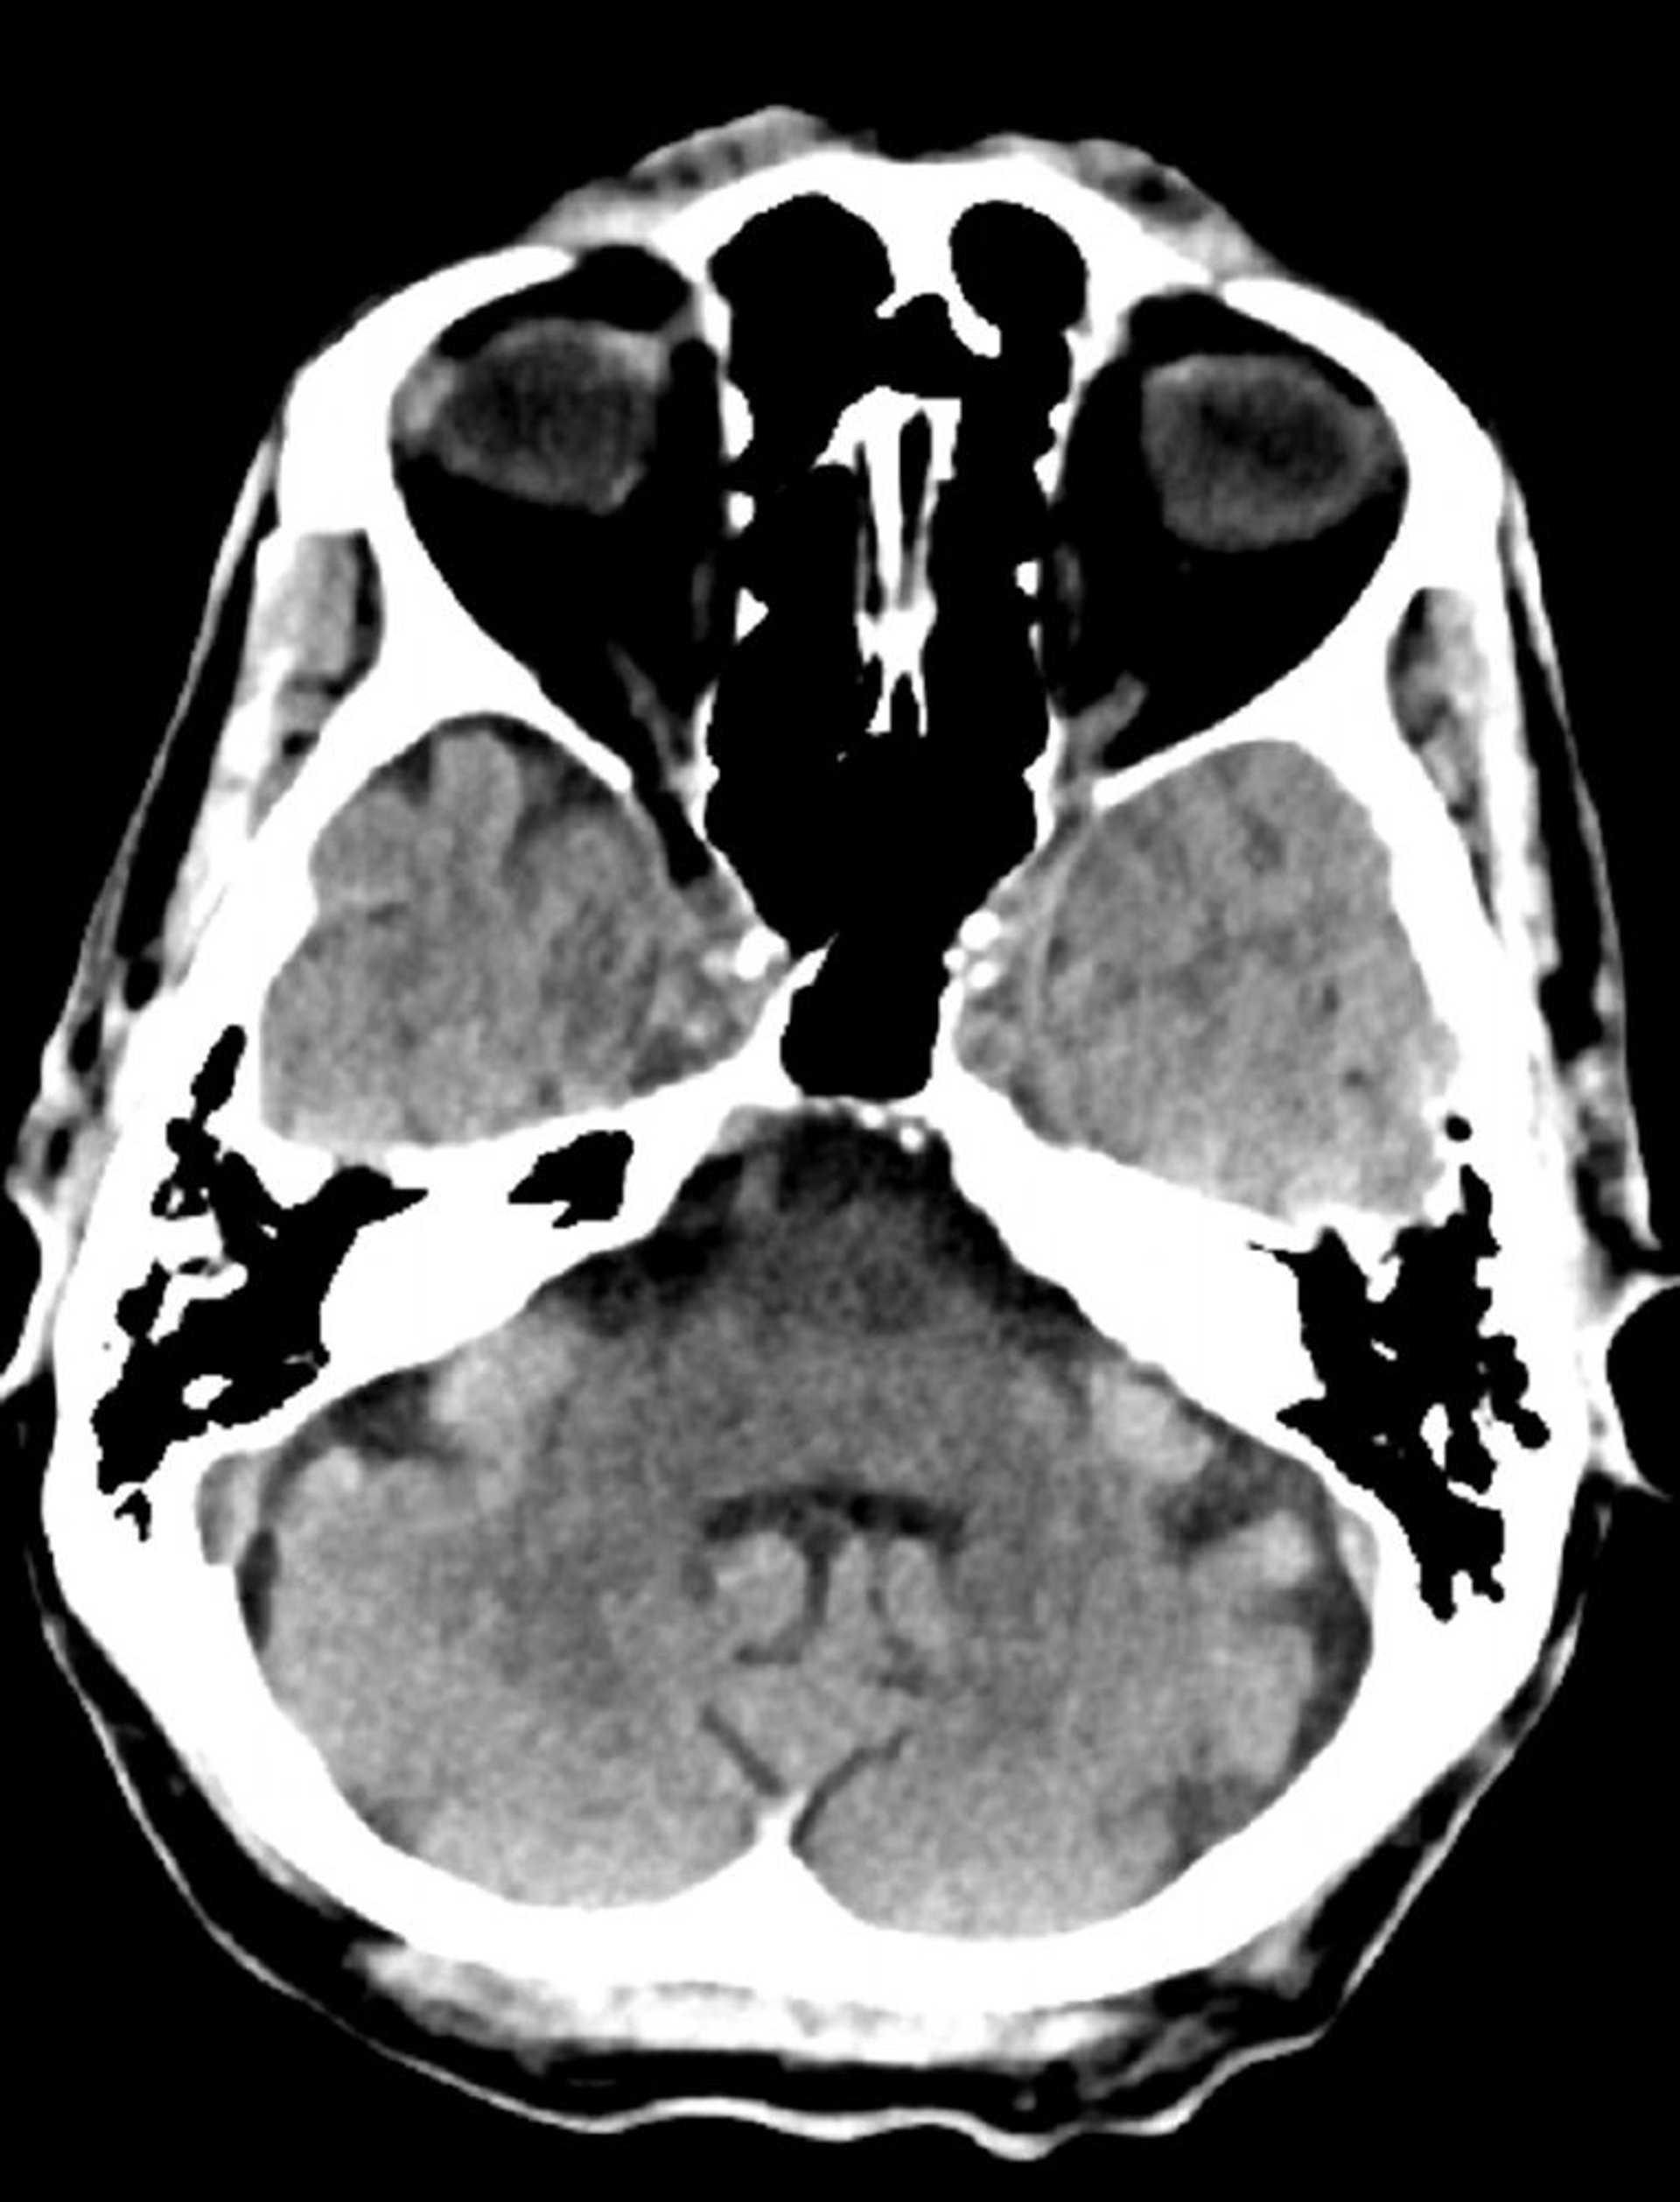

TC de crânio normal (adulto, idade 74) – Diapositivo 8

Essa é uma TC normal da cabeça de um adulto com 74 anos. Quando comparada com a tomografia computadorizada normal da cabeça da pessoa de 30 anos de idade, os ventrículos e sulcos são maiores. Esses achados são normais nessa faixa etária.